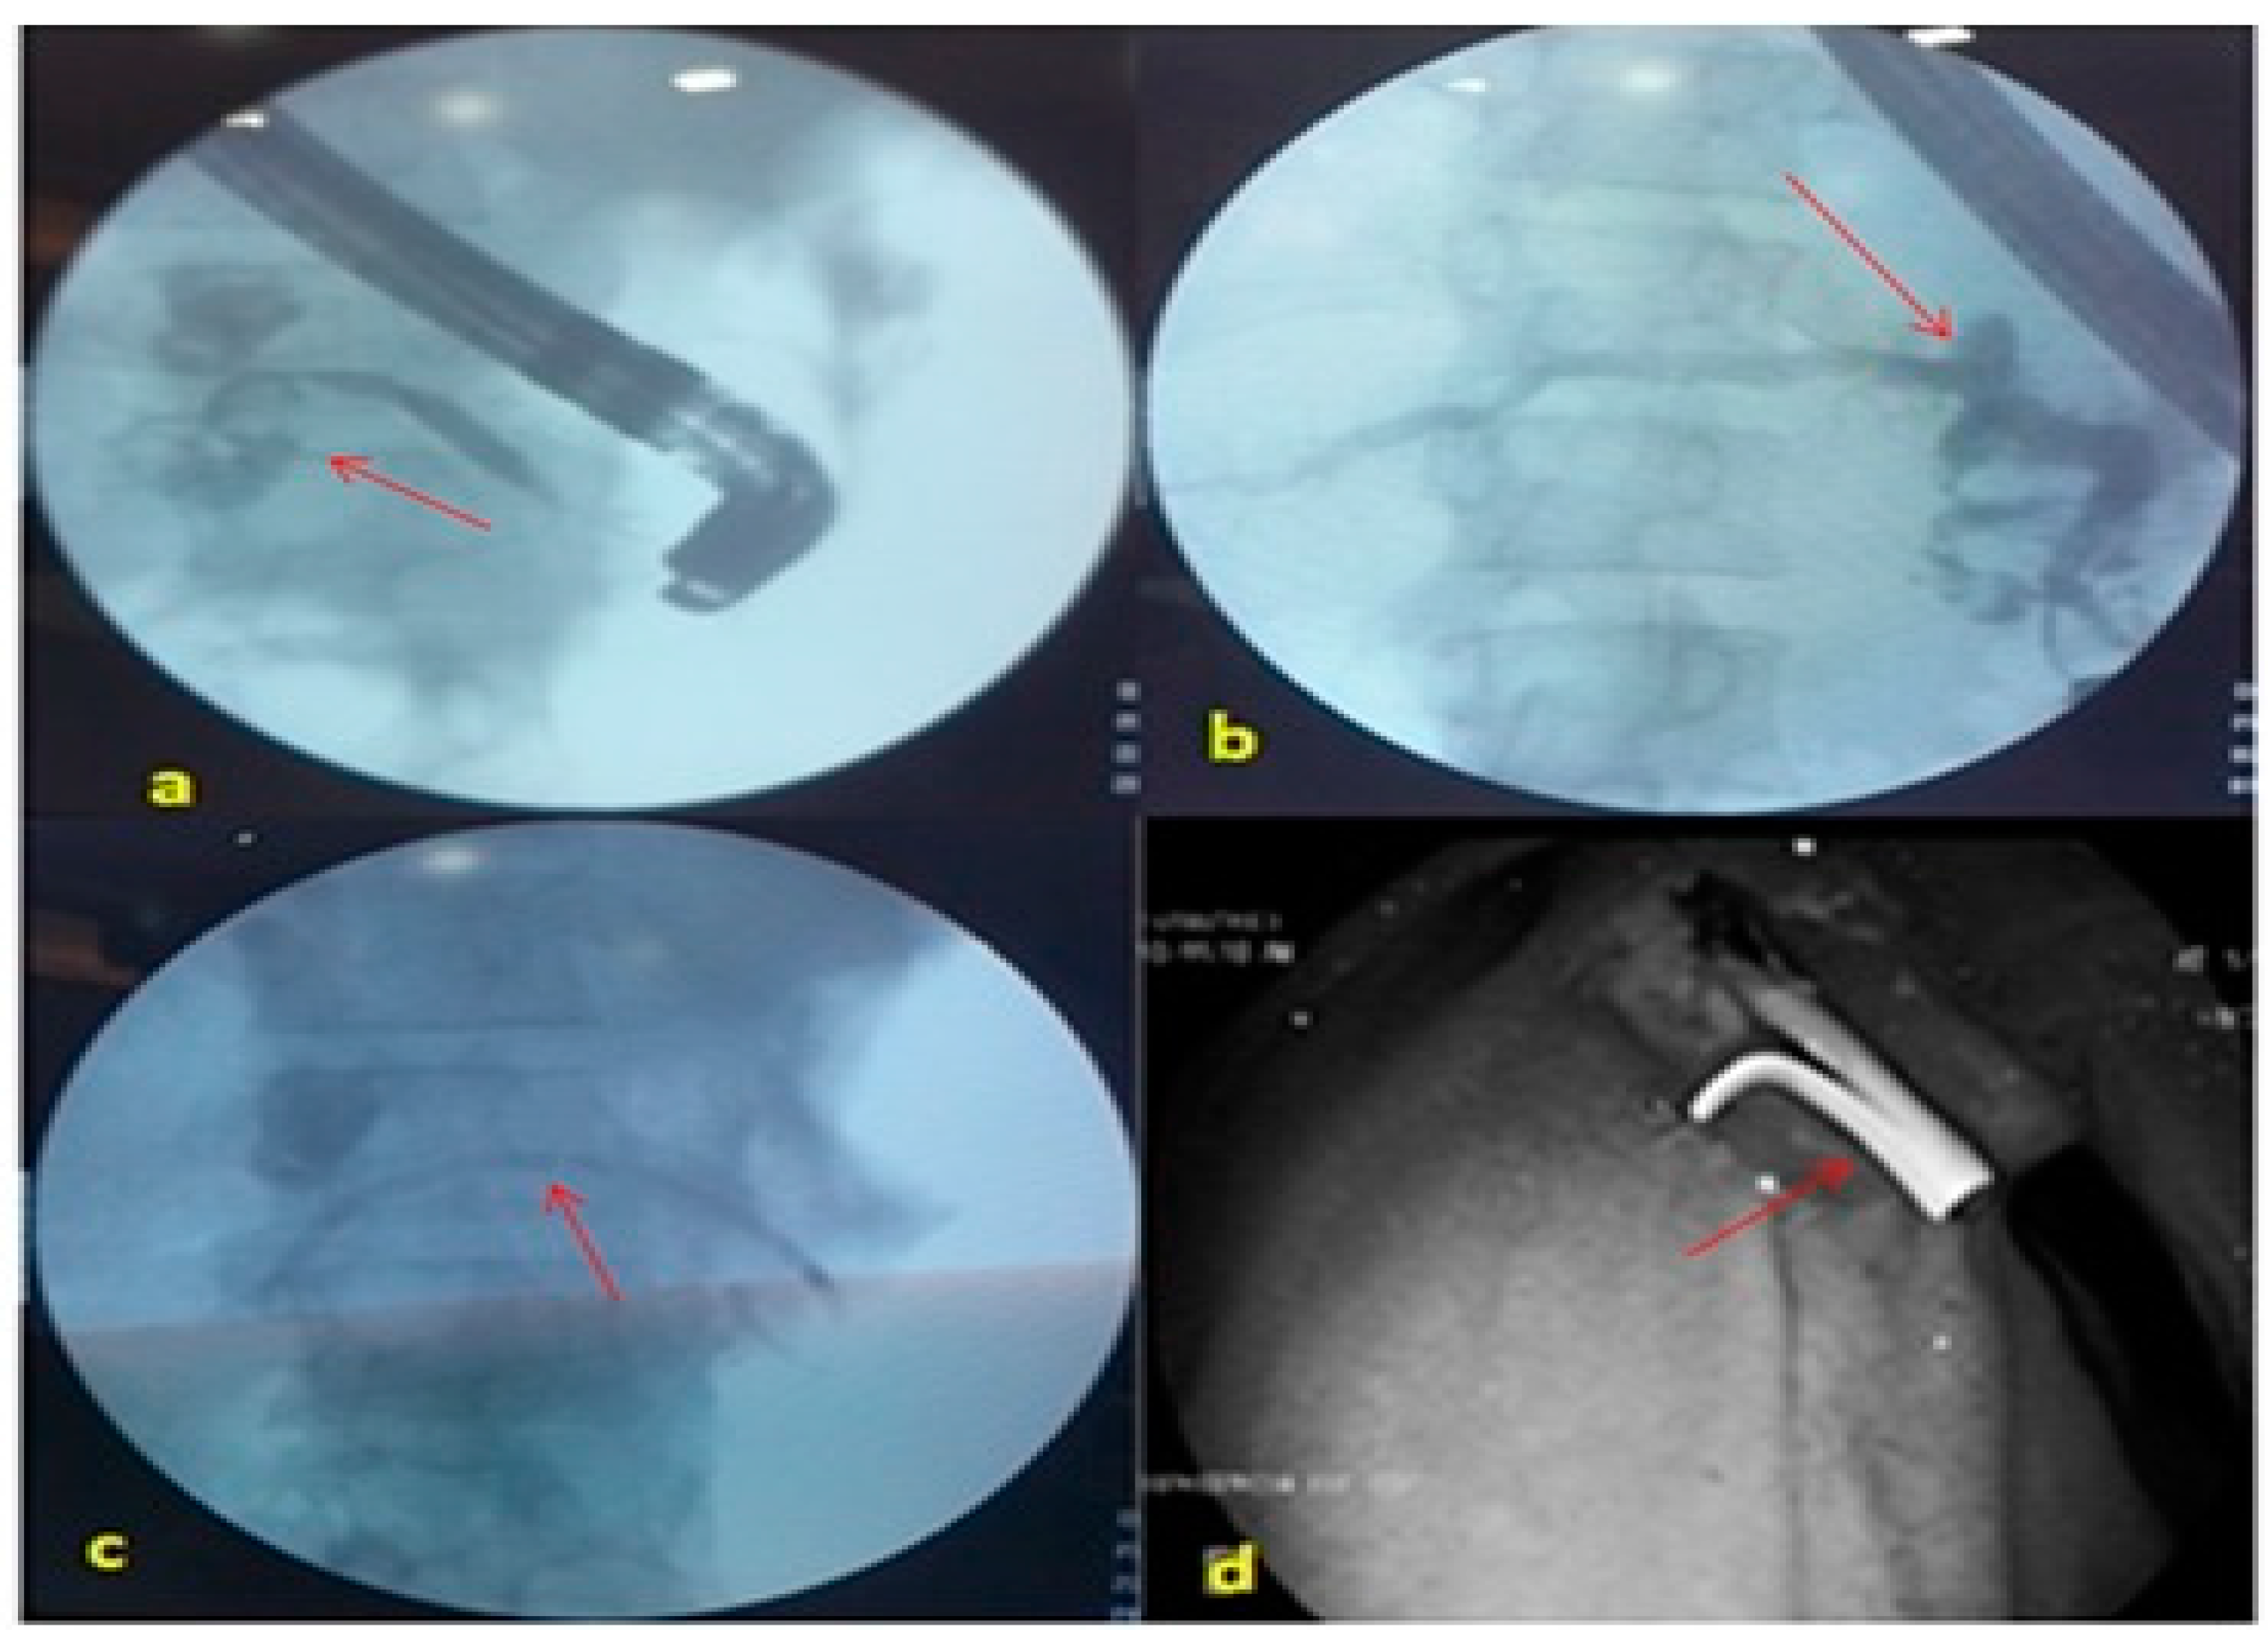

2.3. Procedure